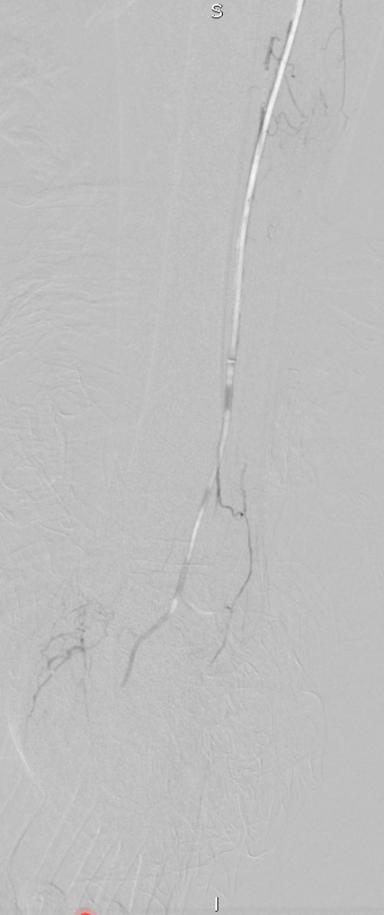

★ Case 1

noproximal stump in SFA,>250mm

★ Case 2

significantdistal collaterals

开通:以内膜下技术为主,逆穿是常用且有效的辅助手段。

预扩:充分预扩张至关重要,需逐级使用高压球囊,最终达到 6mm 直径,以获得足够的管腔。

支架植入:遵循“由远及近”原则,先放置远端 DES,再覆盖中段 VB,最后处理近端。利用 Eluvia 的可调节性优化重叠。

后扩:常规使用 6mm 高压球囊进行后扩张,确保支架充分贴壁和管腔获得。